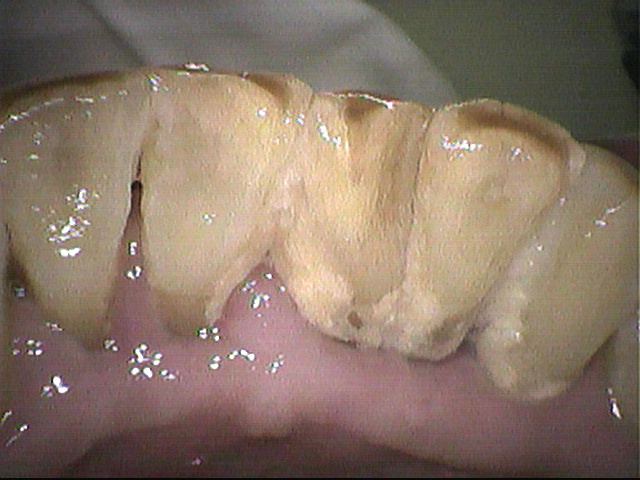

クリーニング前

3ヵ月毎にクリーニングにいらしている患者さんです。

下の前歯に歯石と磨き残しがありましたが

しっかり除去して綺麗になりました。